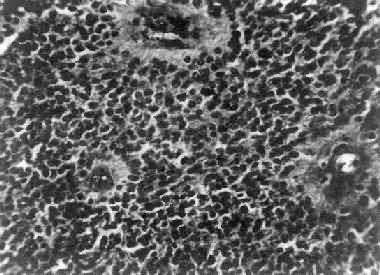

图16-25 室管膜瘤 瘤细胞为圆形或卵圆形,核染色质丰富,胞浆少,可见有细长的胞浆突起与血管相连,呈放射关,形成假菊形团 (二)髓母细胞瘤 髓母细胞瘤(medulloblastoma)好发于儿童,仅次于星形胶质细胞瘤而占第2位,其发生率占儿童颅内肿瘤的25%,发病年龄75%为15岁以下,偶见于成人,男性较女性为多(2~3:1)。 本瘤来源于小脑蚓部的原始神经上皮细胞或小脑皮质的胚胎性外颗粒层细胞,故本瘤主要见于小脑,在儿童多发生于小脑蚓部,在成人则多见于小脑半球。 肉眼观,瘤组织呈鱼肉状,色灰红。镜下,肿瘤由圆形、椭圆形或胡萝卜形细胞构成,胞核着色深,胞浆少而边界不清楚,有多少不等的核分裂像。细胞密集,间质中有纤细的纤维,血管不多。瘤细胞环绕一个嗜银性纤细的神经纤维中心作放射状排列形成典型的菊形团(图16-26),这对髓母细胞瘤的病理诊断有一定的意义。瘤细胞具有向神经元及神经胶质双向分化的潜能,既能向神经母细胞、节神经细胞分化,也能向胶质母细胞、星形胶质细胞分化。如瘤细胞侵入软脑膜,可在蛛网膜下腔脑脊液中广泛播散转移。

图16-26 髓母细胞瘤 瘤细胞较小,着色深,密集排列,有菊形团形成 髓母细胞瘤恶性程度高,预后差。 (三)脑膜瘤 脑膜瘤(meningioma)可来源于脑膜的各组成成分如蛛网膜细胞,纤维母细胞或血管,其中多数来源于蛛网膜颗粒中的蛛网膜细胞。本瘤大多生长缓慢,良性类型可完全无症状,在70岁以上老人的尸检中,发现无症状的脑膜瘤不在少数,无症状脑膜瘤占颅内肿瘤的14%。脑膜瘤患者多为40~50岁中年人,女性较男性多。 肿瘤的好发部位与蛛网膜颗粒所在部位相同,常见于上矢状窦旁大脑镰两侧,蝶骨嵴,嗅沟,小脑脑桥角;在脊髓则以胸段为多见,一般颅内脑膜瘤较脊髓脑膜瘤多2倍。 肉眼观,肿瘤呈球形,分叶状或不规则形,质实或硬,边界清楚,周围脑组织受压成凹陷切迹(图16-27)。少数肿瘤呈斑块状覆盖较广泛区域,甚至整个脑半球,称为斑块型脑膜瘤。肿瘤质地硬,切面灰白色,呈颗粒状、条索旋涡状,有的质地似砂砾样,乃由于有多量砂粒体存在。